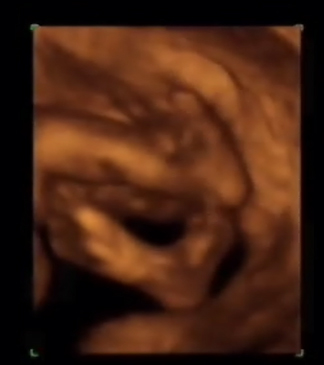

Vídeos Ecografías 4D

Entre las 24 y 31 semanas, es quizás el mejor momento para la realización de ecografías 4D aunque ya han visto que pueden hacerse en cualquier momento. Observen como el feto arrastra su cara sobre la placenta y hace movimientos de succión. ¿Se estará entrenando para la lactancia?

Vea que también los fetos tienen cara de mal genio. Pueden observar perfectamente el tórax y parte del abdomen. ¡Ojo!, la sombra en la cabeza no es el pelo, es un efecto extraño que hacen los ultrasonidos.